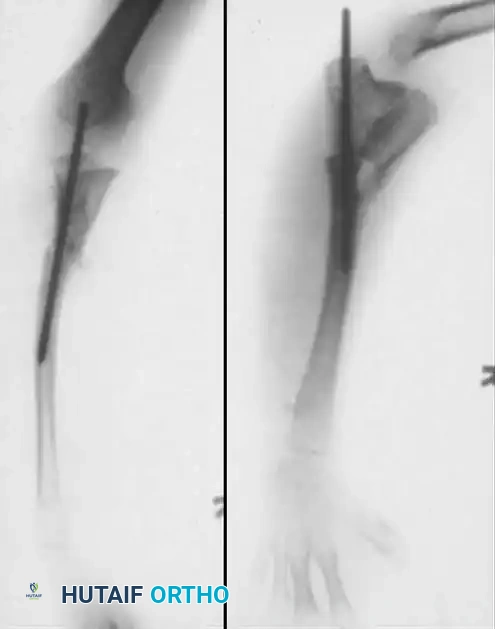

Clinical Radiograph: Preoperative anteroposterior and lateral views demonstrating congenital pseudarthrosis of the ulna with severe radial bowing and secondary dislocation of the radial head.

Surgical Radiograph: Postoperative view following excision of the radial head, creation of a synostosis between the proximal radius and ulna, and rigid fixation with an intramedullary nail.

Final Radiograph: Long-term follow-up demonstrating the final appearance and solid consolidation of the one-bone forearm.